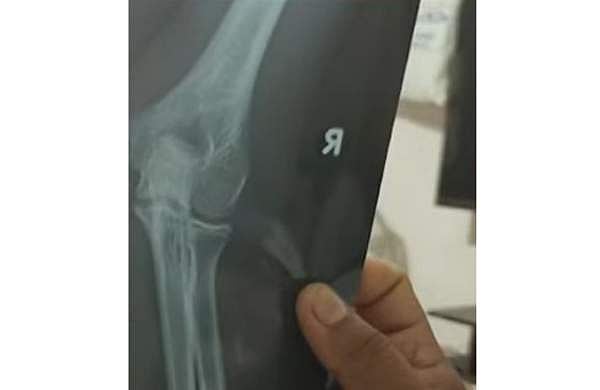

സ്കൂൾ വിദ്യാർഥിയുടെ കൈ ഒടിഞ്ഞതിന്റെ എക്സറേ ദൃശ്യം

ഉടന്‍ തന്നെ പാറശാല താലൂക്ക് ആശുപത്രിയില്‍ കൃഷ്ണ കുമാര്‍ ചികിത്സ തേടി. കൈ ഒടിഞ്ഞതിനെ തുടര്‍ന്ന് കുട്ടിയുടെ കൈയില്‍ പ്ലാസ്റ്റര്‍ ഇട്ടിട്ടുണ്ട്. സംഭവത്തില്‍ സ്‌കൂള്‍ അധികൃതര്‍ രണ്ടു വിദ്യാര്‍ഥികള്‍ക്കെതിരെ പാറശാല പൊലീസില്‍ പരാതി നല്‍കിയിട്ടുണ്ട്.